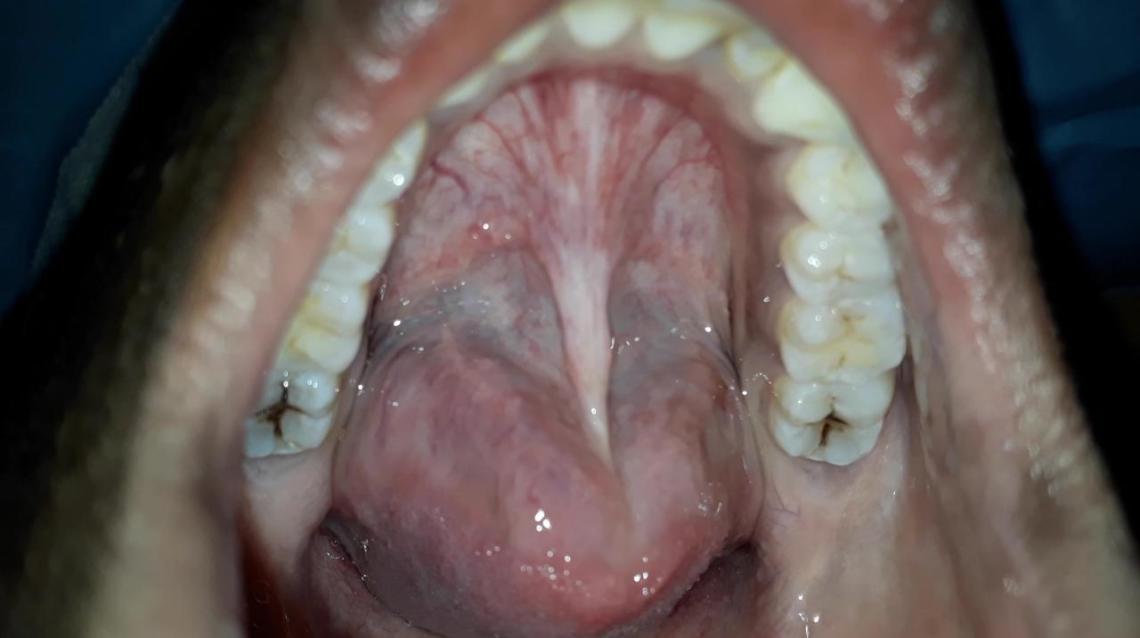

People quite often complain that they have bumps on tongue. Endless fun with a cat or dog. Tongue problems include a variety of symptoms, from pain to changes in color and texture, that can different causes of tongue problems have different symptoms. Warts on the tongue can be discrete bumps on the back of the tongue. Before we delve into what causes the bumps on the back of the tongue, it's important to know that there are two main different types of bumps you may get. Quotes on challenges in life pimple like bumps on the back of the neck. 13.07.2008 · the 'bubbles' in the back of the tongue are probably circumvallate papillae. Tongue is built with oblong shaped muscles that carry nerves and oxygenated blood.

It kind of hurts when moved (not extreme what are these huge bumps on my tongue? This morning i wake up and the back sides of my tongue is sore a little and hurts a little swallow. Depending upon how sore, other symptoms, and\or how curious as to the cause, see pcp, ent or dentist. Bumps on the back of the tongue are typically natural. Warts on the tongue can be discrete bumps on the back of the tongue. Usually, the back of the tongue i the most affected, leading to swelling of taste buds at the back of tongue more than on the tip and sides. Bumps on tongue and bumps on the back of the tongue could be scary if you don't know what caused them. The tongue naturally has bumps known as papillae and those on the back of the tongue are larger than those on the front. Endless fun with a cat or dog. Before we delve into what causes the bumps on the back of the tongue, it's important to know that there are two main different types of bumps you may get. Not bad enough to really pay attention.by this afternoon the very back of my ton… read more. This is a common problem. We all have several hundre d bumps on our tongues called papillae, also known as the taste buds.